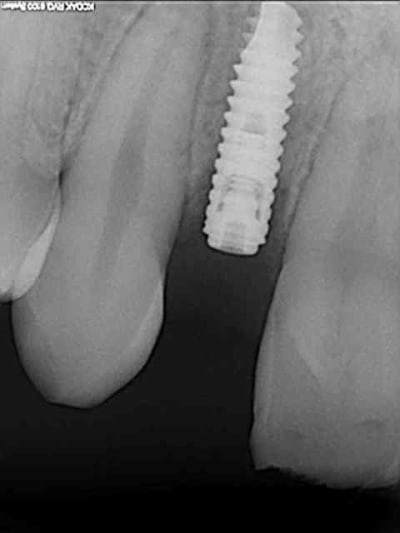

tes implants 12 et 13 n'ont pas le même niveau d'enfouissement, tu n'as pas peur d'une lyse osseuse de 13 pour venir au niveau du col de 12 ?

01/09/2010 à 16h54

- pilier zircone esthétique Axiom

tu as perdu un peu d'os au col, ça serait du à l'expansion ????